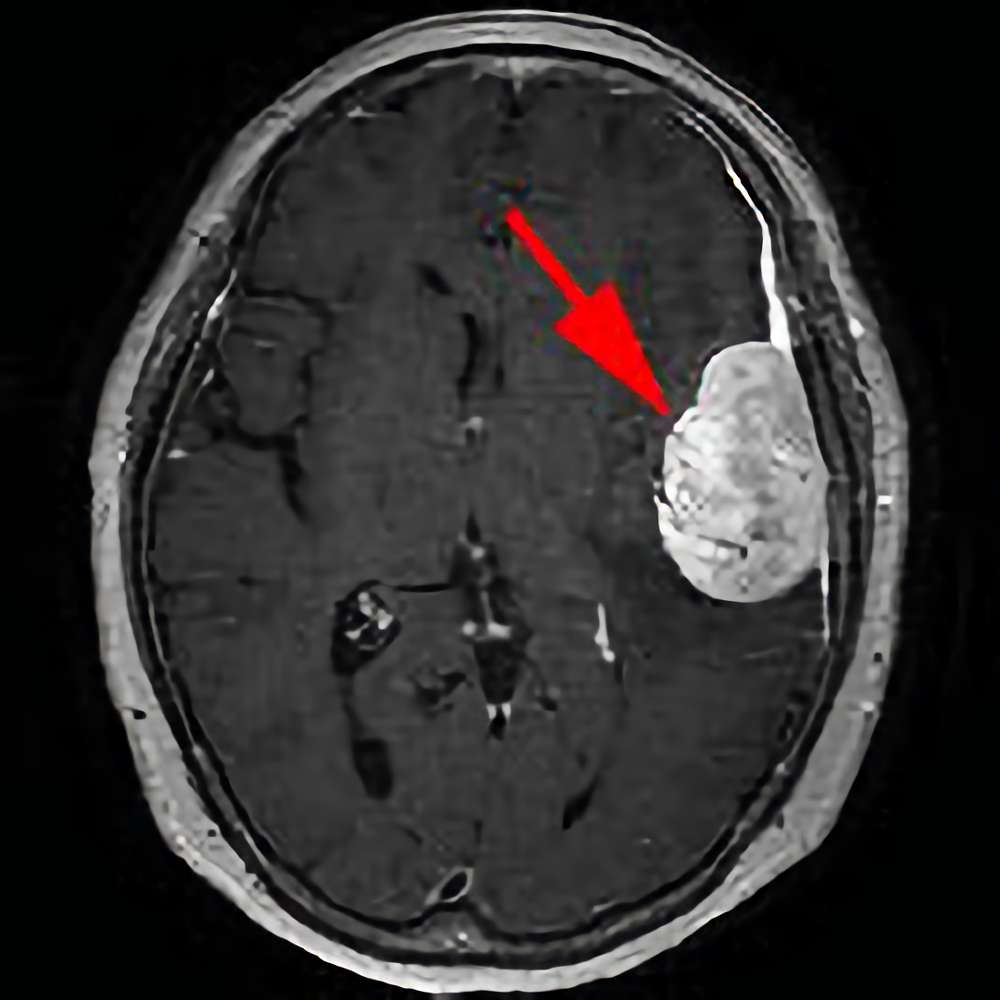

断層撮影

手術前1

手術前2